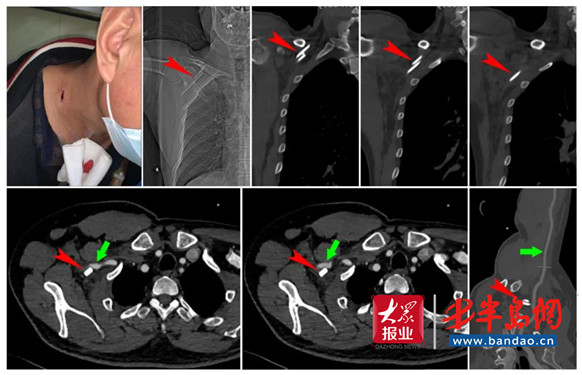

患者傷口及術前影像檢查結果(紅色箭頭所指為異物,綠色箭頭所指為大血管)

經過仔細查體發現,患者頸部右側有長約2厘米的傷口,患者肩部、肘部及腕手部各關節活動正常,僅右手虎口區有麻木感。於是,迅速制定了綜合會診方案:即刻完善新冠篩查流程、相關影像檢查及術前檢查,進壹步了解異物毗鄰情況,制定更加詳細的手術方案。檢查結果很快通過PACS工作站上傳到醫院內網,各科值班醫生仔細研究討論,殘留玻璃異物位於右側鎖骨下,並向前外下方走行,直至胸壁。異物緊鄰鎖骨下動靜脈、臂叢神經,尤其是鎖骨下動脈的壹條分支甲狀頸幹(編者注:鎖骨下動脈的分支之壹,頸部及甲狀腺的主要營養血管)更是緊貼異物,並推測其早期活動性出血應該是甲狀頸幹的伴行靜脈出血,後經壓迫後斷端凝結而止血。同時,患者右手虎口區麻木,考慮是玻璃戳入時傷及臂叢神經所致,術中可視情況給予修補。考慮受傷部位血管、神經密集,且損傷結構主要為臂叢神經,會診醫生壹致贊同由擅長臂叢神經診治的手足外科作為牽頭科室,耳鼻咽喉頭頸外科、胸外科、創傷骨科密切配合,共同進行手術。

作為主刀醫生,手足外科副主任劉金偉回顧整個救治過程,仍感到危險重重、如履薄冰、步步驚心。他說:“術前計劃時,我們已經做好了各項應急措施,大量備血、鎖骨截骨、血管吻合、心肺復蘇等時刻准備啟動,各兄弟科室人員就在手術台旁,時刻准備參加戰斗……患者很幸運,戳入的玻璃總長約12厘米,緊貼大血管、神經前方,刺入後斷為叁段。正如術前判斷,鎖骨下動脈的分支甲狀頸幹破裂、伴行靜脈完全斷裂、臂叢神經外膜破裂,分別給予修補、結扎。”